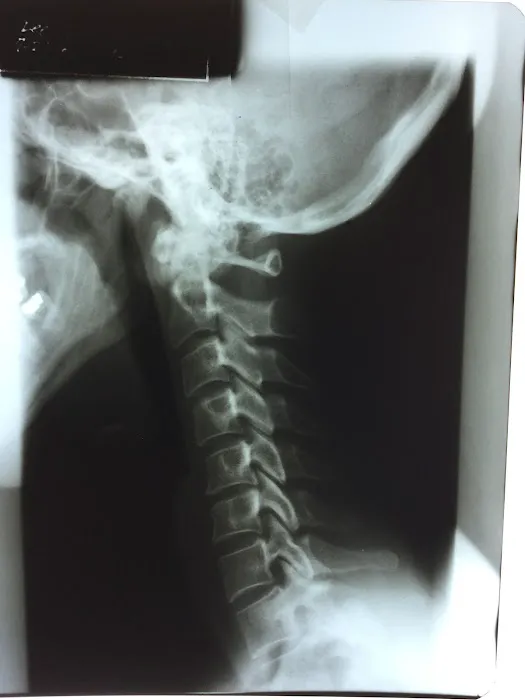

- X-Ray Diagnostics: On-site imaging for accurate diagnosis of musculoskeletal conditions.